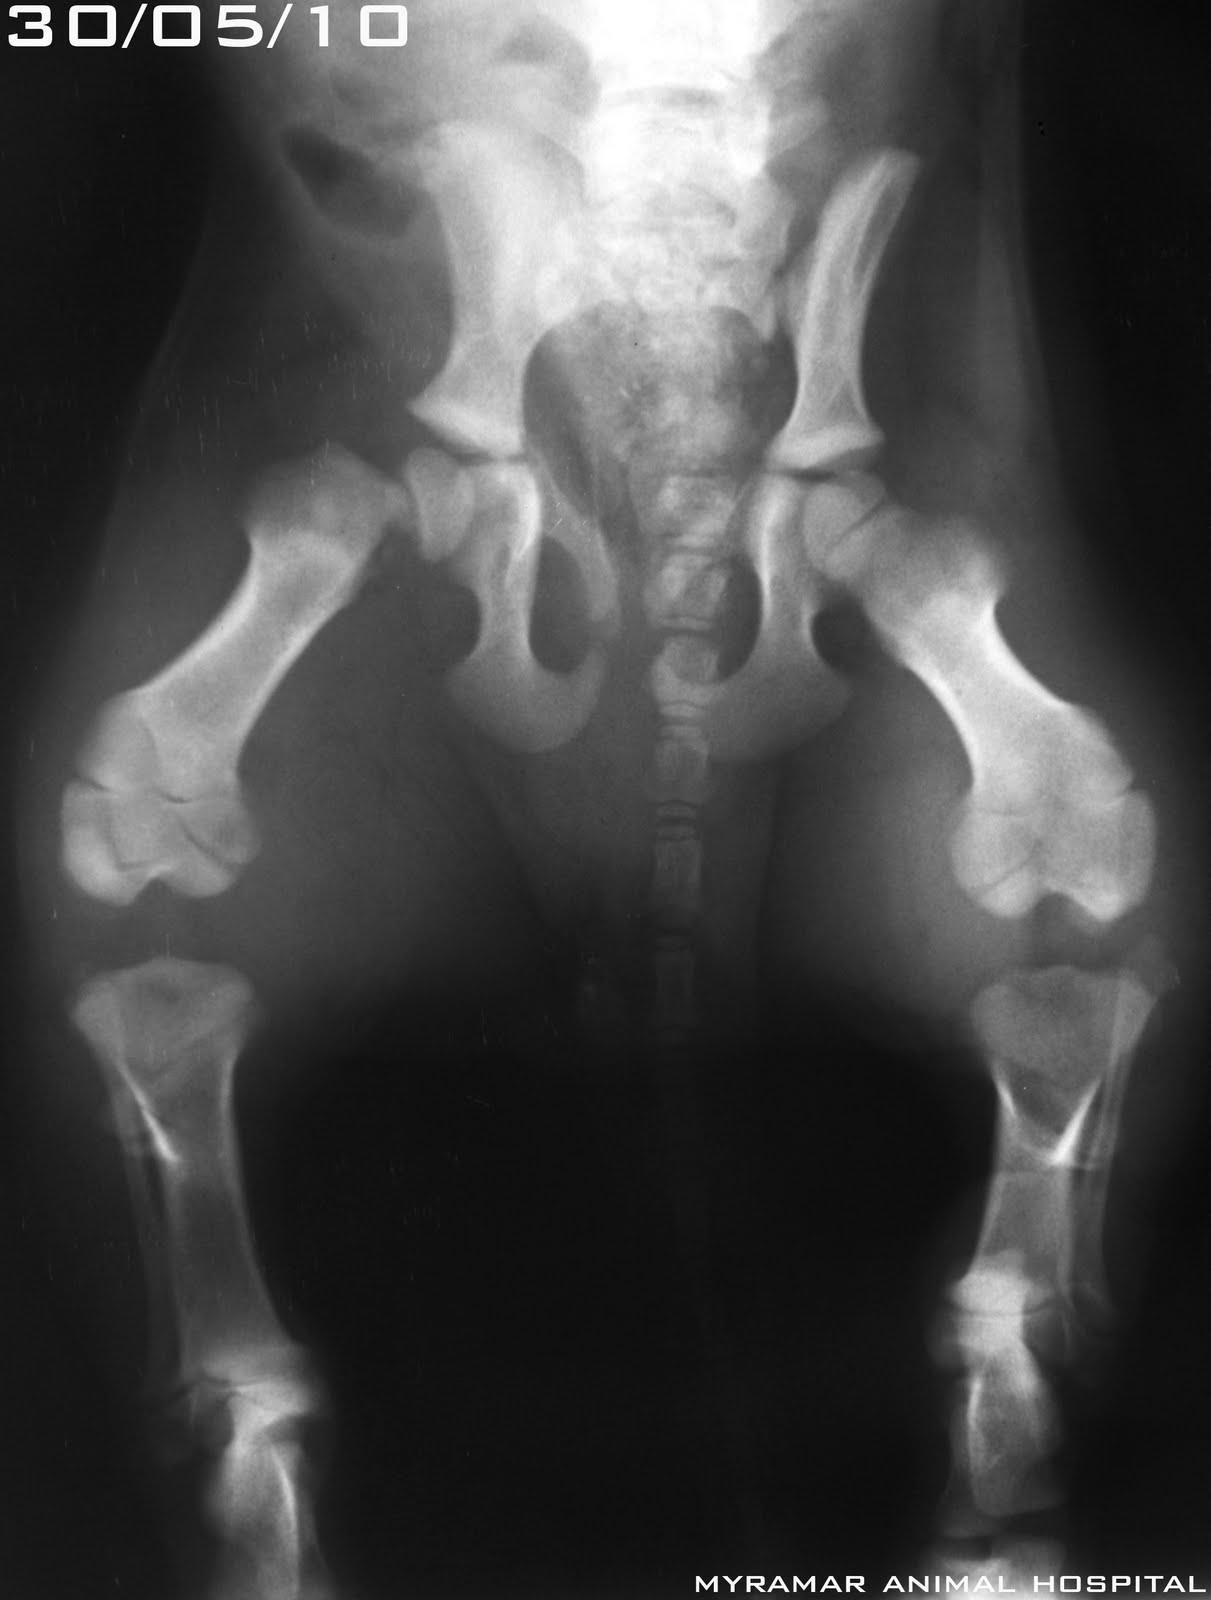

Apolo, bosque de Noruega de 14 meses y 3.8 kg, llega referido con una fractura diafisaria de fémur de cuñas no reducibles. Class AOVET. 32-B3.

Bajo el concepto de estabilidad relativa se reduce utilizando placa LCP synthes 2.7mm con 4 tornillos LHS 2.7mm y un tornillo de cortical 2.7mm. Se refuerza con aguja de Kirschner centromedular de 1.8mm.

Se presentan radiografías pre y postquirgicas del caso.